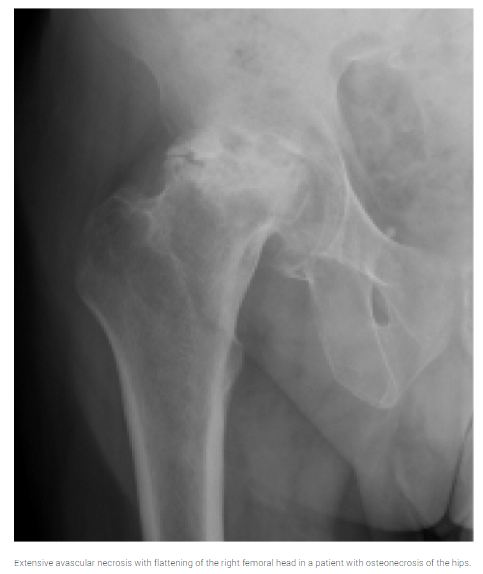

Studies estimate a three- to sixfold increased risk of reduced bone mineral density in patients with HIV infection. Preliminary work also suggests an increased prevalence of fractures. Various antiretrovirals have been associated with osteopenia and osteoporosis, although other factors (e.g., weight, nadir CD4 lymphocyte count, menopausal status, chronic steroid use) may play a role. Given the lack of data, osteoporosis screening for patients with HIV infection remains somewhat controversial.

Extensive avascular necrosis with flattening of the right femoral head in a patient with osteonecrosis of the hips.